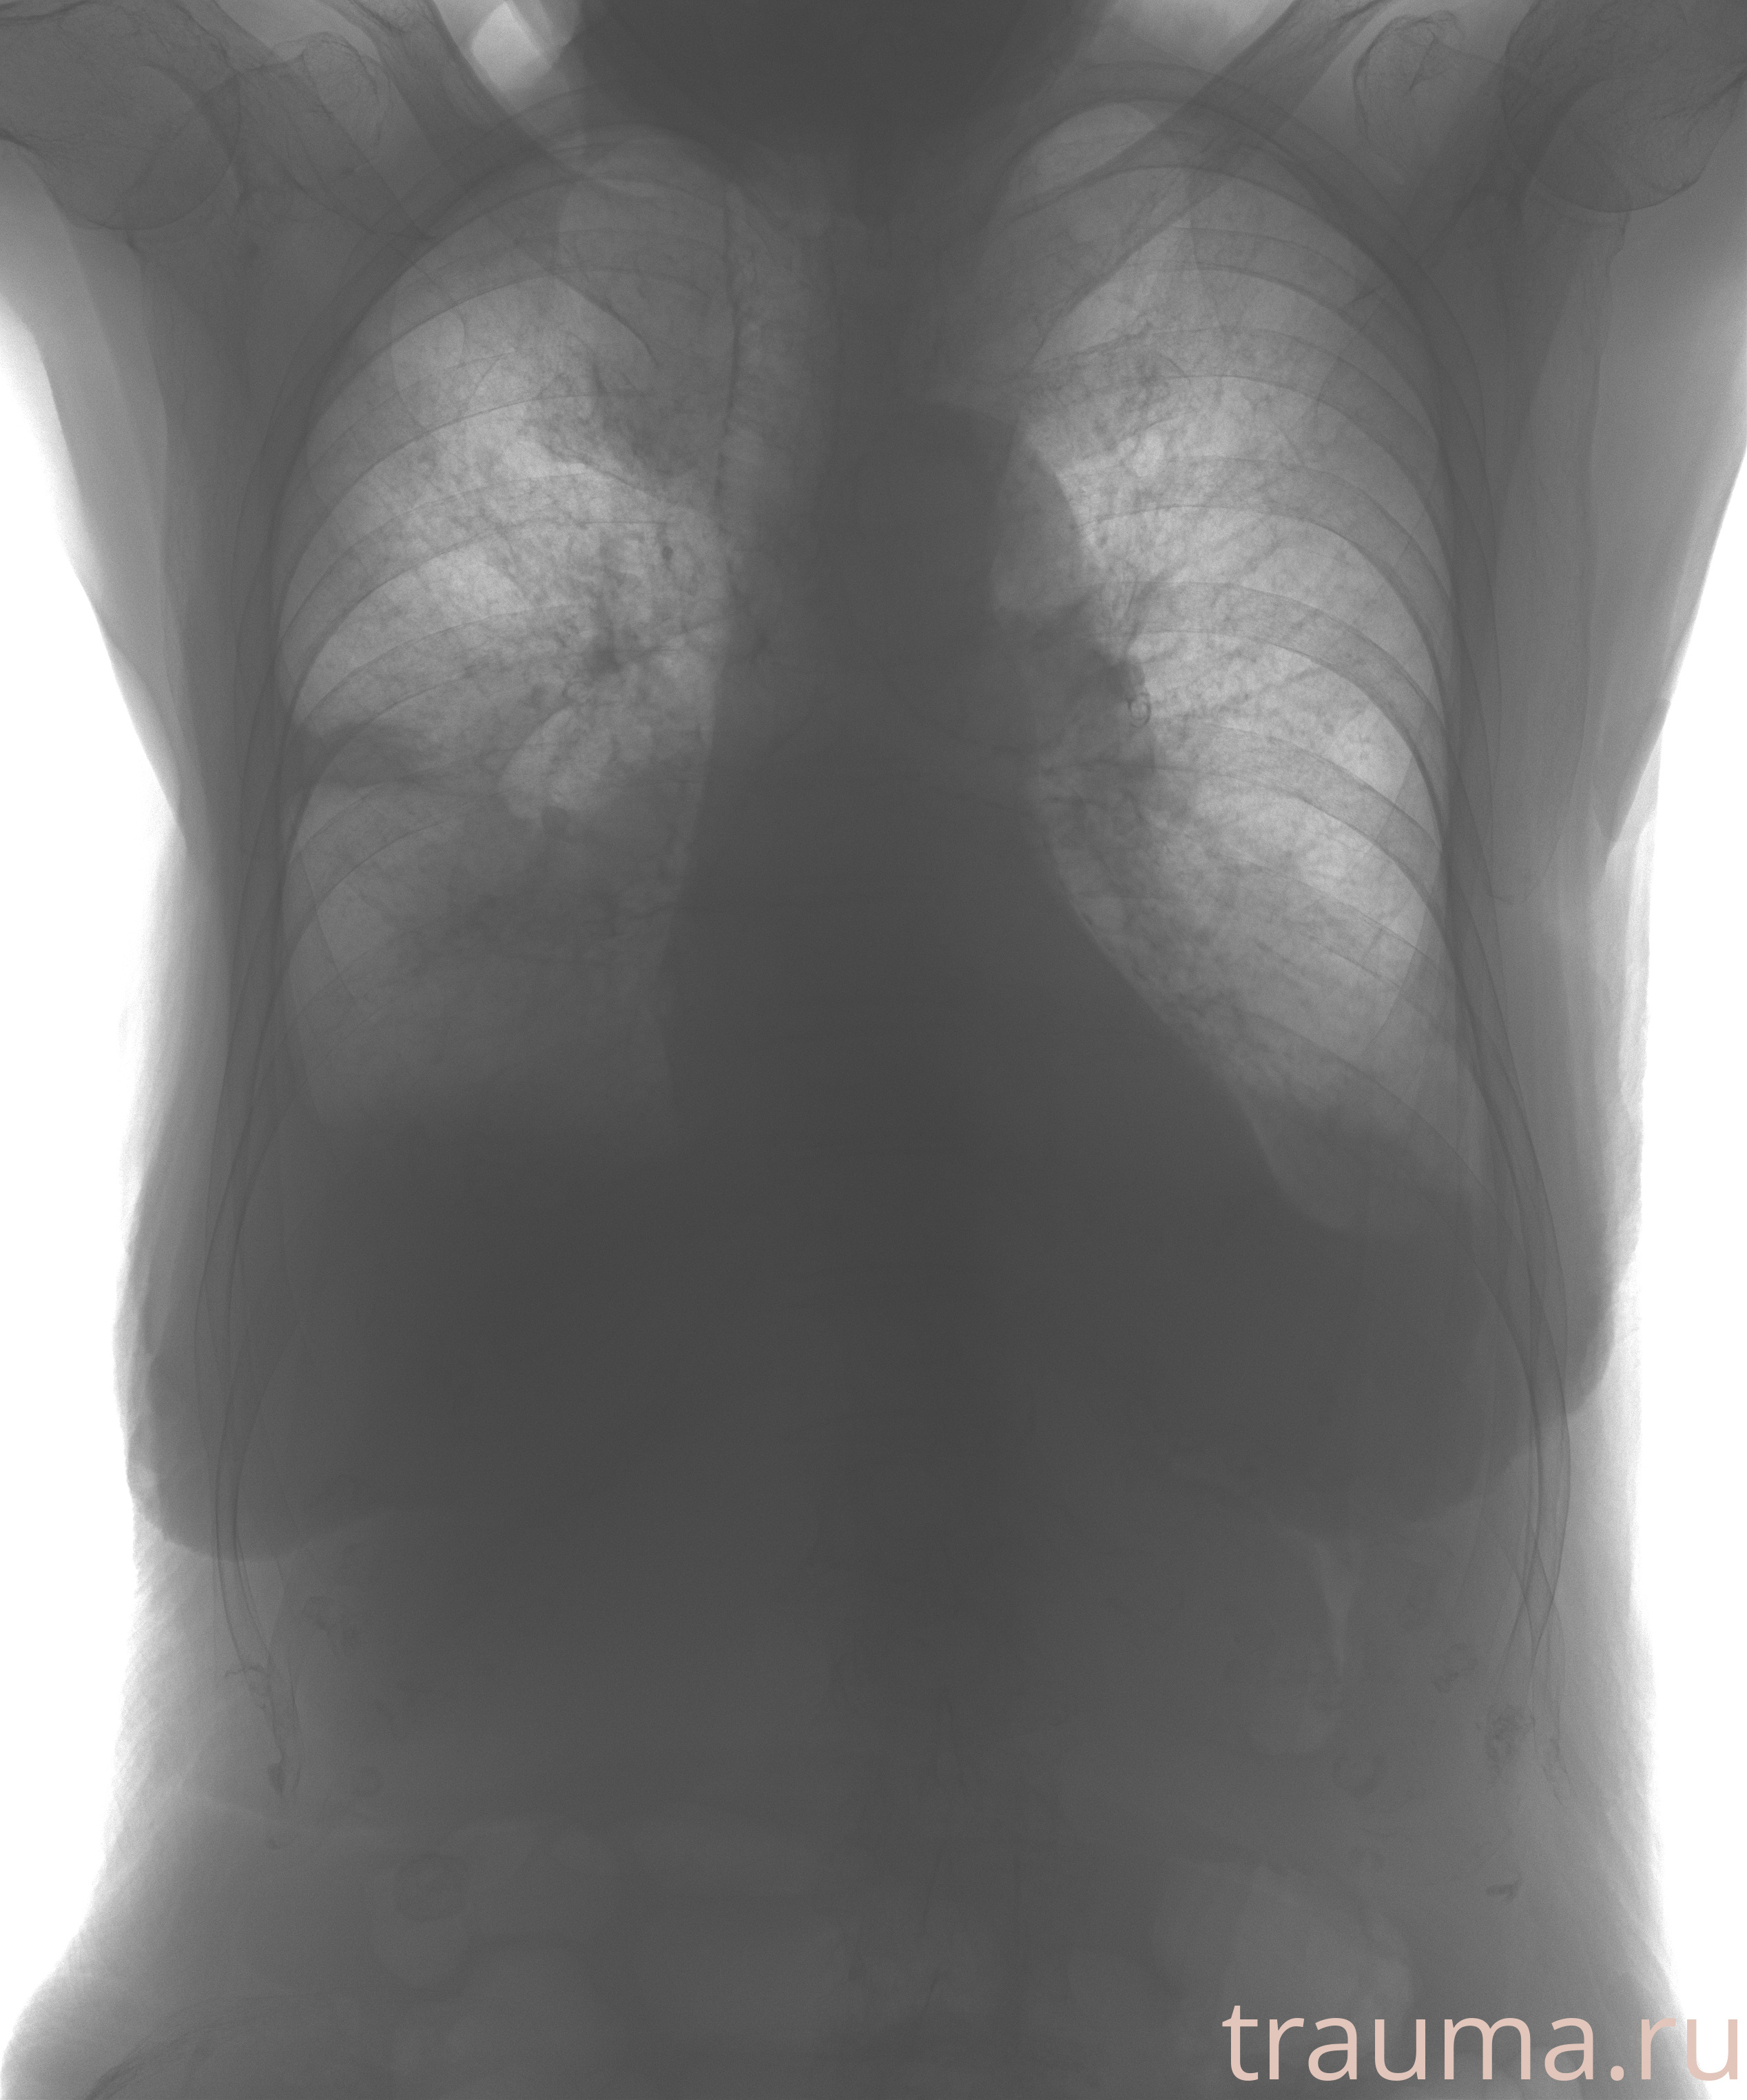

Рентген на дому: по вашему адресу приезжает врач-рентгенолог, травматолог-ортопед с мобильным рентгеновским аппаратом, проводит диагностику травмы или заболевания, делает необходимые рентгенограммы, дает рекомендации по дальнейшему лечению. Получить качественные снимки в домашних условиях возможно благодаря уникальной методике, разработанной МосРентген Центром для института  Склифосовского

при переломе шейки бедра и пневмонии от компании МосРентген Центр - партнера Института имени Склифосовского